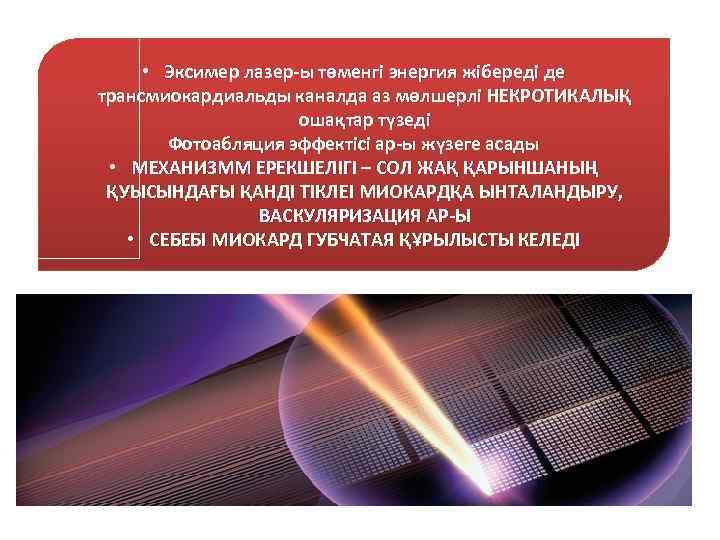

• Эксимер лазер-ы төменгі энергия жібереді де трансмиокардиальды каналда аз мөлшерлі НЕКРОТИКАЛЫҚ ошақтар түзеді Фотоабляция эффектісі ар-ы жүзеге асады • МЕХАНИЗММ ЕРЕКШЕЛІГІ – СОЛ ЖАҚ ҚАРЫНШАНЫҢ ҚУЫСЫНДАҒЫ ҚАНДІ ТІКЛЕІ МИОКАРДҚА ЫНТАЛАНДЫРУ, ВАСКУЛЯРИЗАЦИЯ АР-Ы • СЕБЕБІ МИОКАРД ГУБЧАТАЯ ҚҰРЫЛЫСТЫ КЕЛЕДІ

• Эксимер лазер-ы төменгі энергия жібереді де трансмиокардиальды каналда аз мөлшерлі НЕКРОТИКАЛЫҚ ошақтар түзеді Фотоабляция эффектісі ар-ы жүзеге асады • МЕХАНИЗММ ЕРЕКШЕЛІГІ – СОЛ ЖАҚ ҚАРЫНШАНЫҢ ҚУЫСЫНДАҒЫ ҚАНДІ ТІКЛЕІ МИОКАРДҚА ЫНТАЛАНДЫРУ, ВАСКУЛЯРИЗАЦИЯ АР-Ы • СЕБЕБІ МИОКАРД ГУБЧАТАЯ ҚҰРЫЛЫСТЫ КЕЛЕДІ